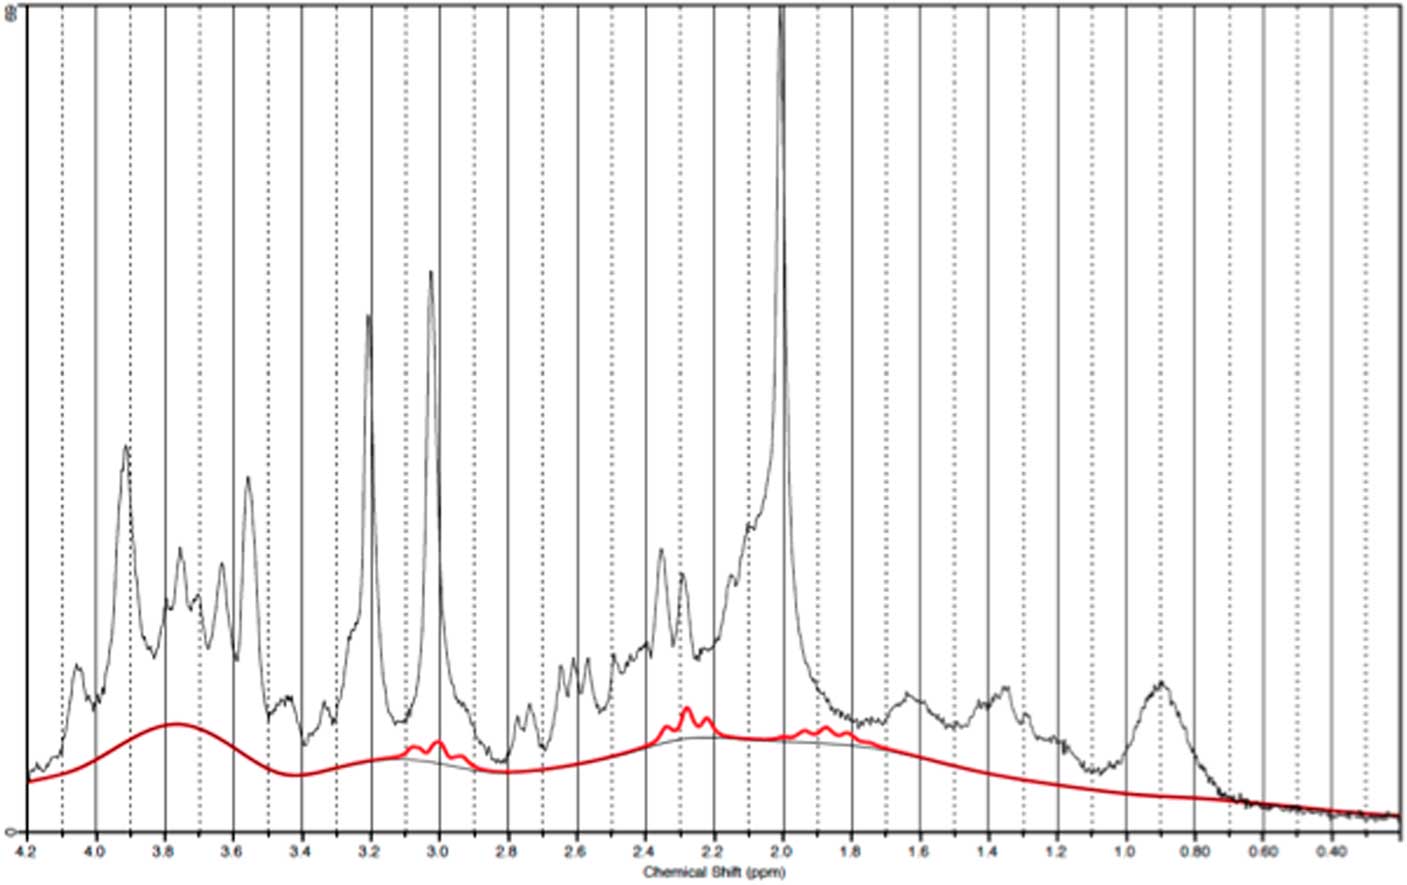

GABA measurements in OCC

Data from one occipital follow-up scan was discarded due to poor spectral quality. Figure 6 illustrates a representative spectra from OCC and Fig. 7 an individual plot for the GABA signal in OCC. When performing direct comparison between patients at baseline and healthy subjects, we found no significant difference in GABA/Cr ratios t(21)=0.37, p=0.72. The same applied when comparing pre- and post-ECT GABA/Cr levels in patients t (20)=0.78, p=0.47. Moreover, no significant correlation was found between pre-ECT GABA/Cr levels and HAM-D17 ratings (p=0404).

Fig. 6 Example of a representative spectrum from the occipital cortex. The raw data are plotted as a thin black curve. The thick red curve is the LcModel fit to this data. The baseline is also plotted as a thin black curve. At the top are plotted the residuals.

Fig. 7 Example of an individual plot for γ-aminobutyric acid from the occipital cortex. The raw data are plotted as a thin black curve. The thick red curve is the LcModel fit to this data.